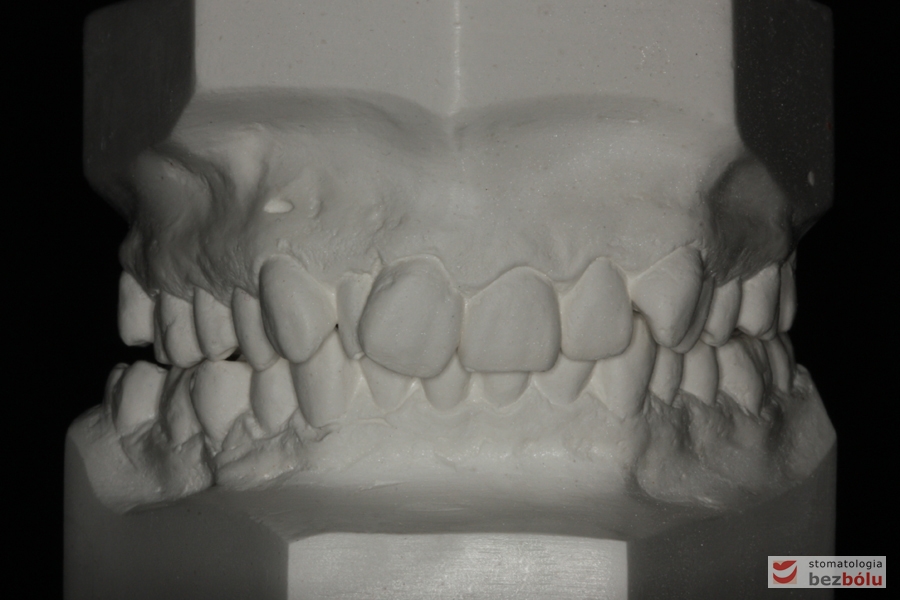

Pacjentka lat 26 zgłosiła się do gabinetu celem korekcji uśmiechu. Głównym zmartwieniem były problemy estetyczne, które znacznie wpływały na jakość życia pacjentki. Wykonano leczenie zachowawcze zębów oraz analizę cefalometryczną i analizę modeli diagnostycznych. Zaplanowano leczenie aktywne aparatem DAMON dla szczęki i żuchwy, które trwało 2 lata. Po fazie leczenia aktywnego rozpoczęto leczenie retencyjne z użyciem szyny tłoczonej dla szczęki i retainera stałego dla żuchwy.